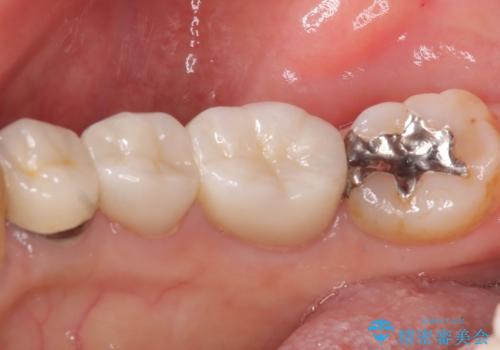

- 主訴:下の歯に詰まっている銀が笑うと見えて嫌だから白くしたい

右下7番目の歯に保険適用のメタルインレーが入っており、大きなう蝕などは認めなかったため概形は大きく変えずセラミックインレーへやり替えとなりました。

やり替える過程で古い裏層材やカリエスは全て除去し、新たにCR裏層を行っています。